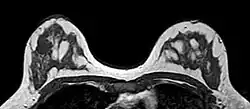

O sistema de relatórios e dados de imagem da mama (BI-RADS, do inglês Breast Imaging Reporting and Data System) é uma sistematização internacional para avaliação mamária, interpretação e laudos de exames de imagem da mama. No início, era utilizado apenas à mamografia, mas também é usado na ultrassonografia e ressonância magnética.[1]

- A categoria BI-RADS 1 quer dizer laudo de mamografia negativa, não há presença de massas ou calcificações suspeitas. As mamas são simétricas, sem massas, distorções de arquitetura ou calcificações suspeitas. Não há risco de câncer.

- A categoria BI-RADS 2 quer dizer laudo mamográfico contendo achados benignos, sem indicações de malignidade. Tem o risco do desenvolvimento de câncer idêntico ao BI-RADS 1, os médicos radiologistas decidem descrever os achados benignos incluindo fibroadenomas calcificados, calcificações múltiplas de origem secretora, cistos oleosos, lipomas, galactoceles e hamartomas de densidades mistas.

- A categoria BI-RADS 3 apresenta achados benignos menores que a categoria 2, e possuem pequena probabilidade de desenvolvimento maligno menor que 2%, recomenda-se fazer o controle semestral por 1 a 2 anos. Se nesse período continuar estável, será classificado como BI-RADS 2 (não há necessidade de realização de biópsia).